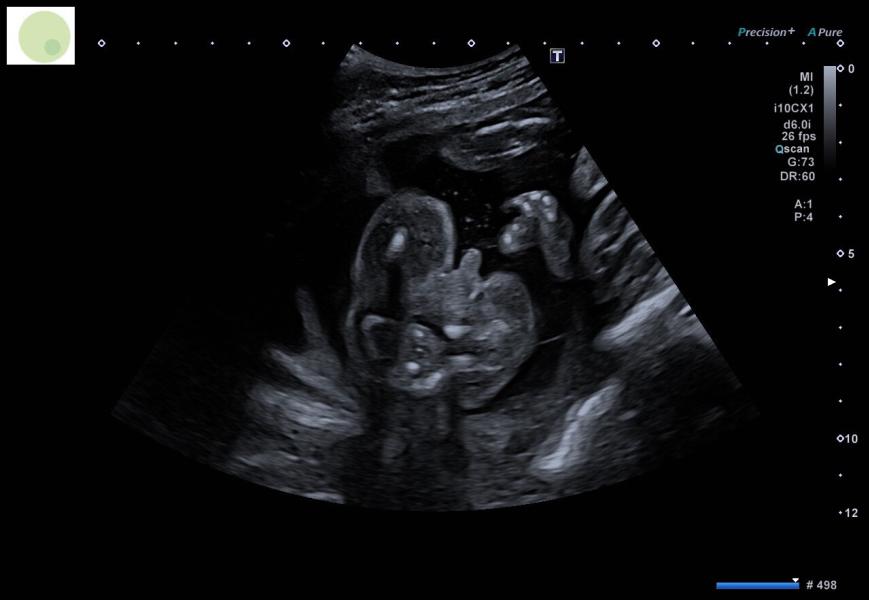

Я говорила что напишу что же нам скажет узист в пренатальном центре. Напомню что гинеколог сказала что увидела что-то в желудке у ребенка.

Так вот, у ребенка все чисто в желудке 🙌🏼

Оказывается у меня из-за гематомы, плавают кусочки крови в водах и ребенок иногда может как бы глотнуть её. Ничего страшного в этом нет. Ребенок полностью здоров ❤️🤞🏼на фото подтверждение, что это все таки мальчик 🤣